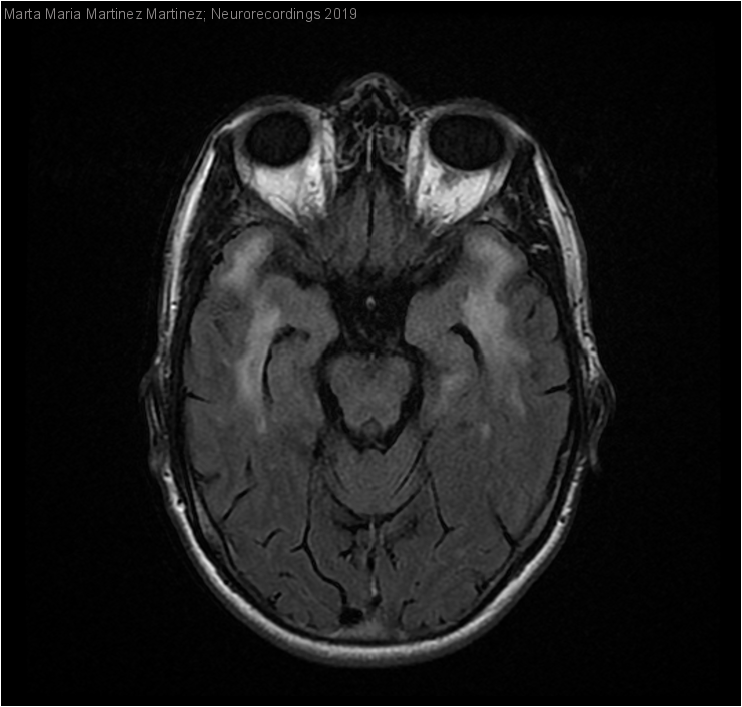

Hombre | 47 años

Diagnóstico final: Enfermedad de CADASIL (Arteriopatía cerebral autosómica dominante con infartos subcorticales y leucoencefalopatía)

Varón de 47 años llevado a urgencias por cuadro brusco de desorientación y confusión. No antecedentes de interés personales ni familiares. Asoció algún episodio de temblor generalizado no sugestivo de crisis convulsiva. 2-3 semanas había presentado...